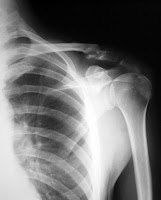

For those of you who don't follow me on twitter or facebook or know me personally, you may not be aware that Jason (my husband), broke his collar bone this past Saturday. He was playing basketball, went up for a shot, someone fouled him mid-air and he crashed into the gym wall head and shoulder first. Long story short, he's home recovering and the new responsibility has been keeping me busy. He probably won't need surgery but we'll know more in a couple more weeks when he sees his Ortho again.